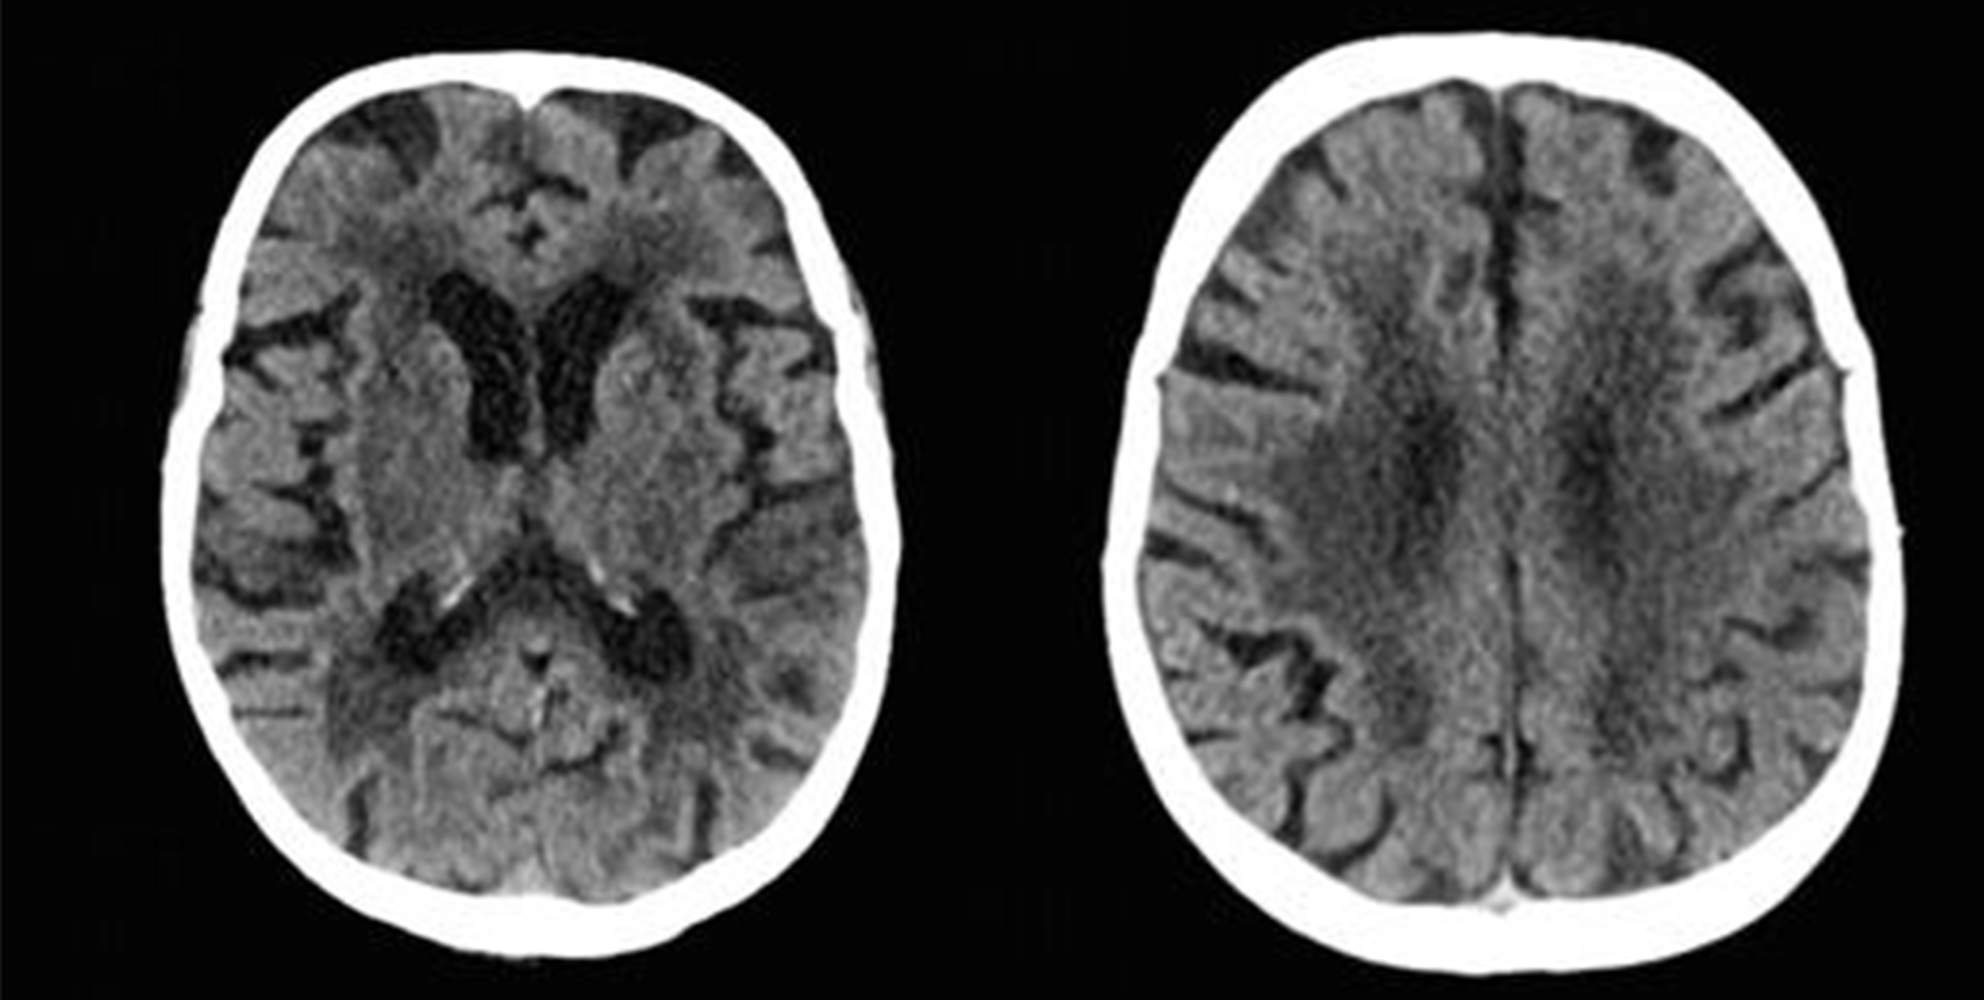

ASPECTS & PC-ASPECTS

Right thalamus Left thalamus midbrain pons Left cere Right cere Right oci Left oci

PC-ASPECT Score: